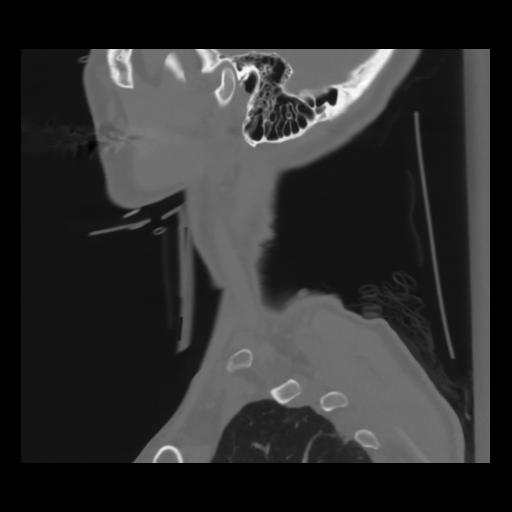

14 P.BLANDAS,,Sagittal,2.000,P.BLANDAS,Sagittal,